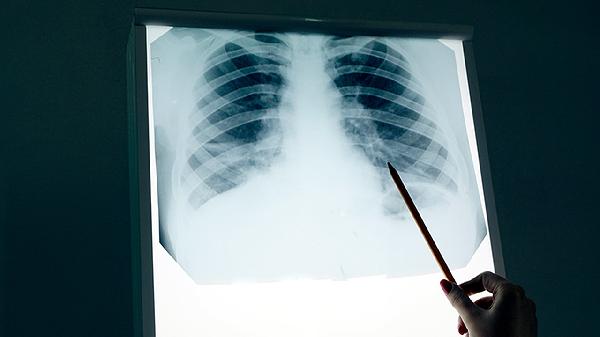

2、肺癌的诊断方法:胸部CT是诊断肺癌的首选检查,可清晰显示肺部病变的位置和范围。X光片可作为初步筛查手段,支气管镜可直接观察气道内部并取活检。PET-CT有助于评估肿瘤的代谢活性和转移情况。血液肿瘤标志物检测如CEA、CYFRA21-1等可辅助诊断。